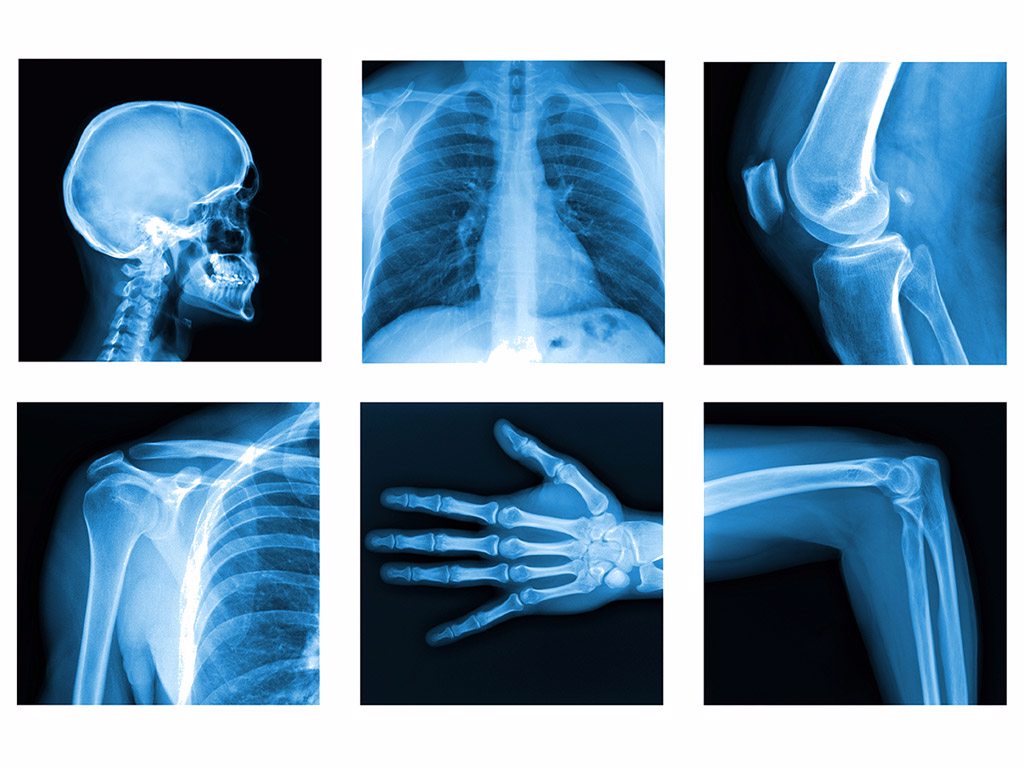

خدمات تصویربرداری پزشکی درمانگاه مشیری | تشخیص دقیق با پیشرفتهترین تجهیزات

خدمات تصویربرداری پزشکی یکی از مهمترین و پایهایترین مراحل تشخیص بیماریها در علم پزشکی است. کیفیت این تصاویر نقش مستقیم در سرعت و دقت تشخیص دارد و هرچه دستگاهها پیشرفتهتر و تکنسینها باتجربهتر باشند، احتمال خطا کمتر و نتایج قابل اعتمادتر میشود.

در درمانگاه مشیری، ما با بهرهگیری از بهروزترین دستگاههای دیجیتال و تیم متخصص، دقیق و آموزشدیده یکی از کاملترین و ایمنترین مجموعههای تصویربرداری را در اختیار بیماران قرار دادهایم تا روند تشخیص و درمان آنها با بالاترین کیفیت ممکن انجام شود.

هدف ما ارائه خدمات تصویربرداری سریع، ایمن، کماشعه، با وضوح بالا و کاملاً استاندارد است تا بیماران بدون معطلی بتوانند تشخیص دقیق و قابل اعتماد دریافت کنند. از رادیولوژی دیجیتال گرفته تا سونوگرافی تخصصی، ماموگرافی پیشرفته و تصویربرداری OPG و تکدندان—all in one place—همگی در درمانگاه مشیری با کیفیت ممتاز انجام میشود.

رادیولوژی دیجیتال (X-Ray)

چه افرادی باید از خدمات تصویربرداری استفاده کنند؟

بیماران با دردهای استخوانی یا مفصلی

افراد آسیبدیده ناشی از سقوط یا تصادف

بیماران با مشکلات تنفسی

افراد با دردهای شکمی یا لگنی